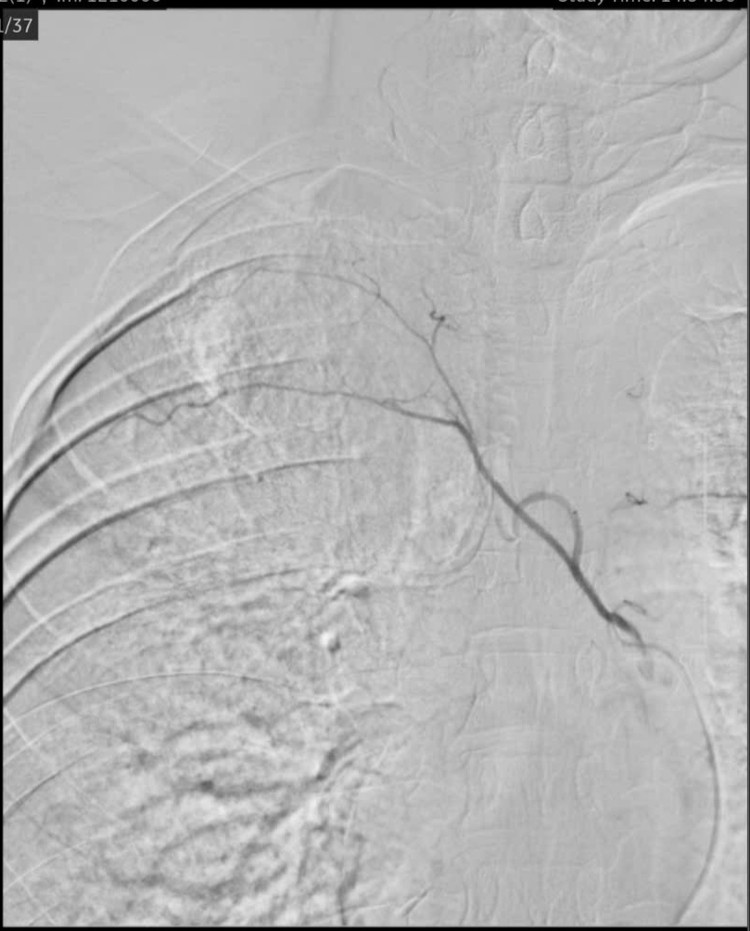

Sau cuộc hội chẩn, ê-kíp thống nhất phương pháp điều trị cho bệnh nhân đó là nút động mạch phế quản phải dưới hướng dẫn của hệ thống chụp mạch số hóa xóa nền DSA, giúp kiểm soát và chấm dứt hoàn toàn tình trạng ho ra máu.

| Hình ảnh sau can thiệp mạch - Ảnh BVCC |

Chỉ 1 giờ sau ca can thiệp, người bệnh đã tỉnh táo, không còn ho ra máu, không đau ngực hay khó thở. Người bệnh sau đó được chuyển qua Khoa Nội Hô Hấp để tiếp tục theo dõi, chăm sóc và điều trị.